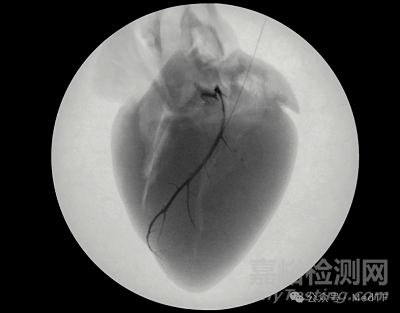

眾所周知目前市場上的植入式心律轉復除顫器(ICD)和起搏器絕大多數產品都需要配套金屬導線來實現治療。但是導線放置是一個很有挑戰(zhàn)手術,例如一些患者的心臟靜脈較小,而導線尺寸相對較大,因此只能放置在心臟外表面附近最大的心臟靜脈中。這導致很多治療效果欠佳。根據臨床研究顯示,多達三分之一的接受電療法治療的患者(包括在左心室壁放置導線)對治療反應不佳。

因此需要有新技術來替代傳統(tǒng)金屬導線,Rhythio Medical開發(fā)的可注射起搏導線Liquid Wire是一個非常有潛力新型替代技術。Liquid Wire是一種可導電的水凝膠,可通過針頭直接輸送到目標組織。注射后,凝膠會形成穩(wěn)定的電接口,與現有植入式心律轉復除顫器(ICD)和起搏器無縫集成,將傳統(tǒng)的高電壓電擊轉化為溫和、患者友好的治療方案。

Liquid Wire植入過程也非常簡單,只需通過一個專有的輸送系統(tǒng)將兩種液體化合物同時注入到患者的心臟靜脈中。在心臟靜脈中兩種化合物反應固化,形成一條深入到心臟靜脈深處的導電水凝膠。